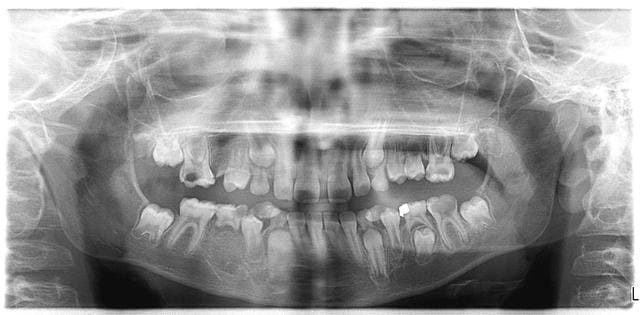

alors je sais que ce n'est pas mon rôle, mais on a un rythme qui fait que je gère les arrivées en urgence : je fais une pano (à moi les oranges en prison, je sais), ma prat la regarde et j'annonce le verdict.

Maintenant on voit plus ça que 1 à 2 fois par an....Cette année, j'ai vu un gamin de 7 ans,la cata; la radio de Sandrine c'est pas grand chose à côté...